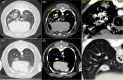

An 8-year-old 24.6 kg mixed breed dog underwent bronchoscopy for evaluation of a persistent progressive cough. Bronchoscopy documented a markedly thick and irregular, cobblestone appearance of the mucosa. A bronchoscopic biopsy was obtained; immediately after the biopsy, a large amount of hemorrhage poured from the endotracheal tube. Multiple efforts to control the hemorrhage were unsuccessful and the dog suffered a cardiopulmonary arrest and could not be revived. A necropsy was performed, which was significant for pallor, evidence of prior heartworm disease, prominent bronchial arteries, and erosion of the submucosal vessels at the site of the biopsy. The cause of death was hemorrhage associated with transbronchial biopsy of an enlarged bronchial artery associated with heartworm disease. This report describes a rare complication of a routine diagnostic procedure.